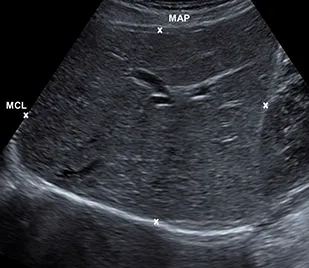

Liver size

Appearance

Measurements

Diameter | Female cm (mean ± SD) | Male cm (mean ± SD) |

Midclavicular line (largest craniocaudal diameter) | 14.9 ± 1.6 | 15.1 ± 1.5 |